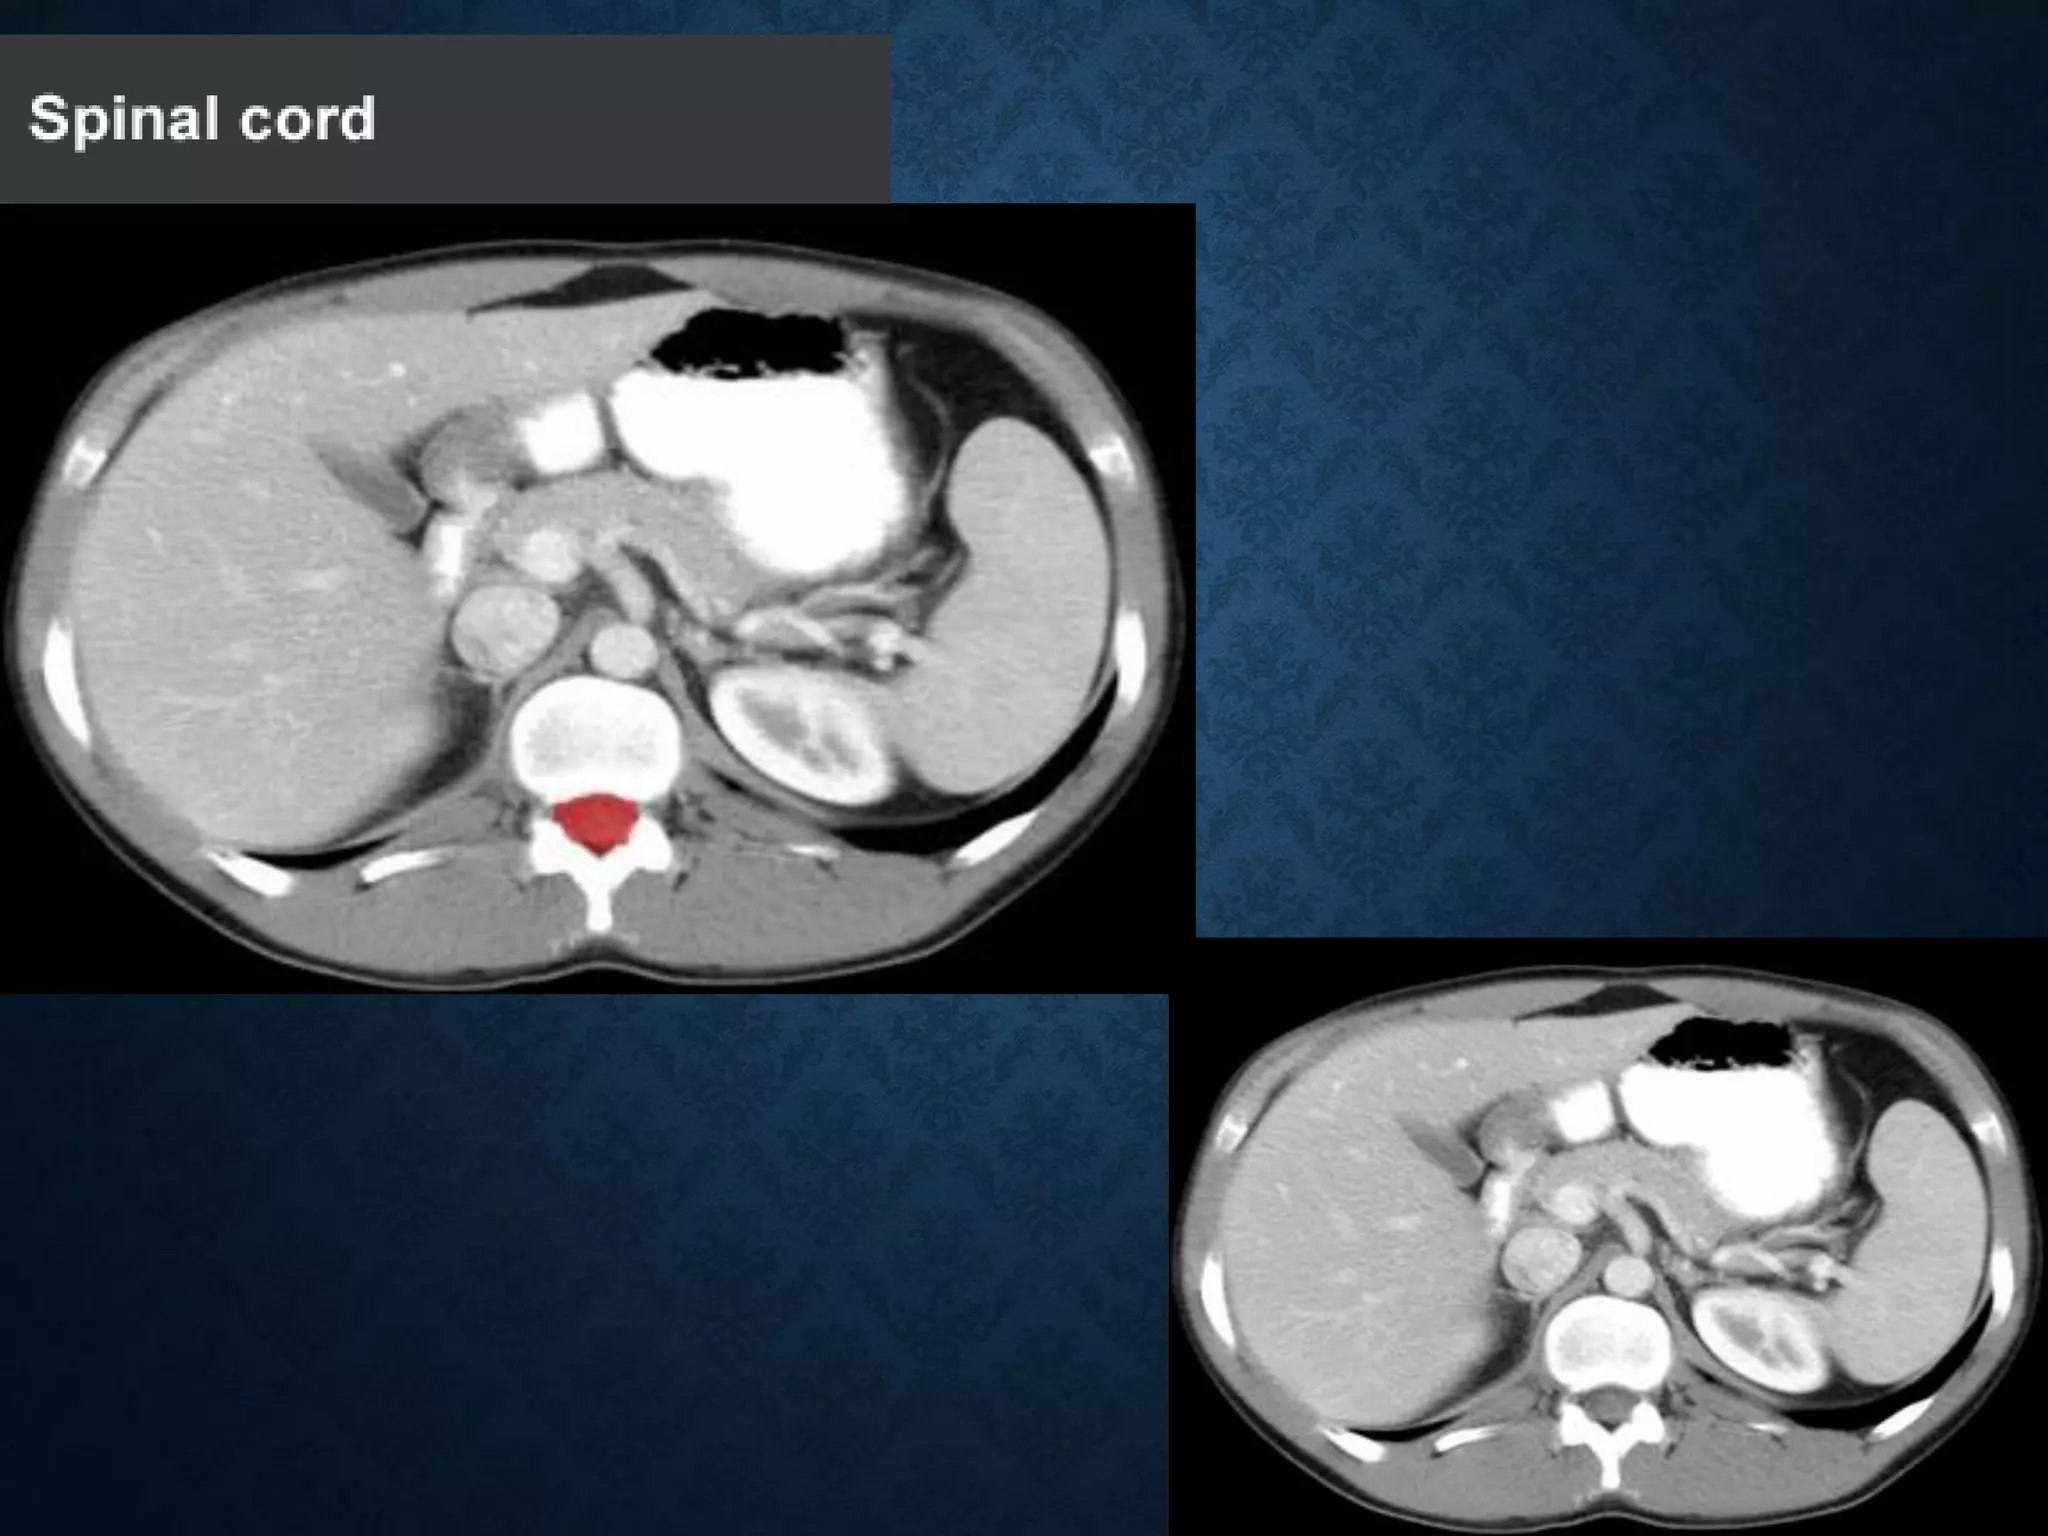

NORMAL ANATOMY- SECTION 8

NORMAL ANATOMY- SECTION 9

NORMAL ANATOMY- SECTION 10

NORMAL ANATOMY- SECTION 11

Normal Anatomy- Section 12